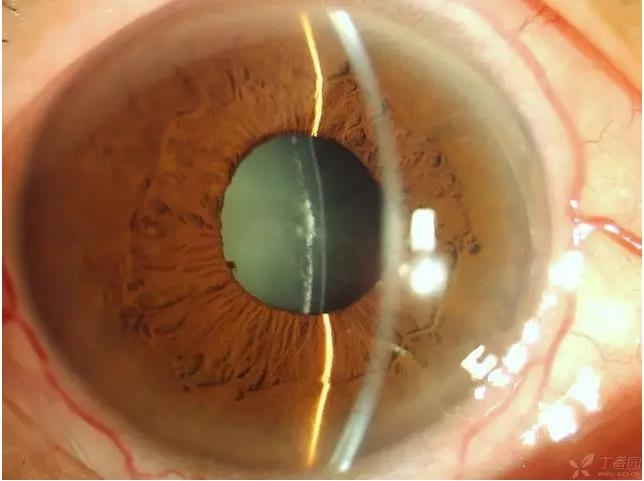

▼ICL术后

实用贴:眼科病例高清图片